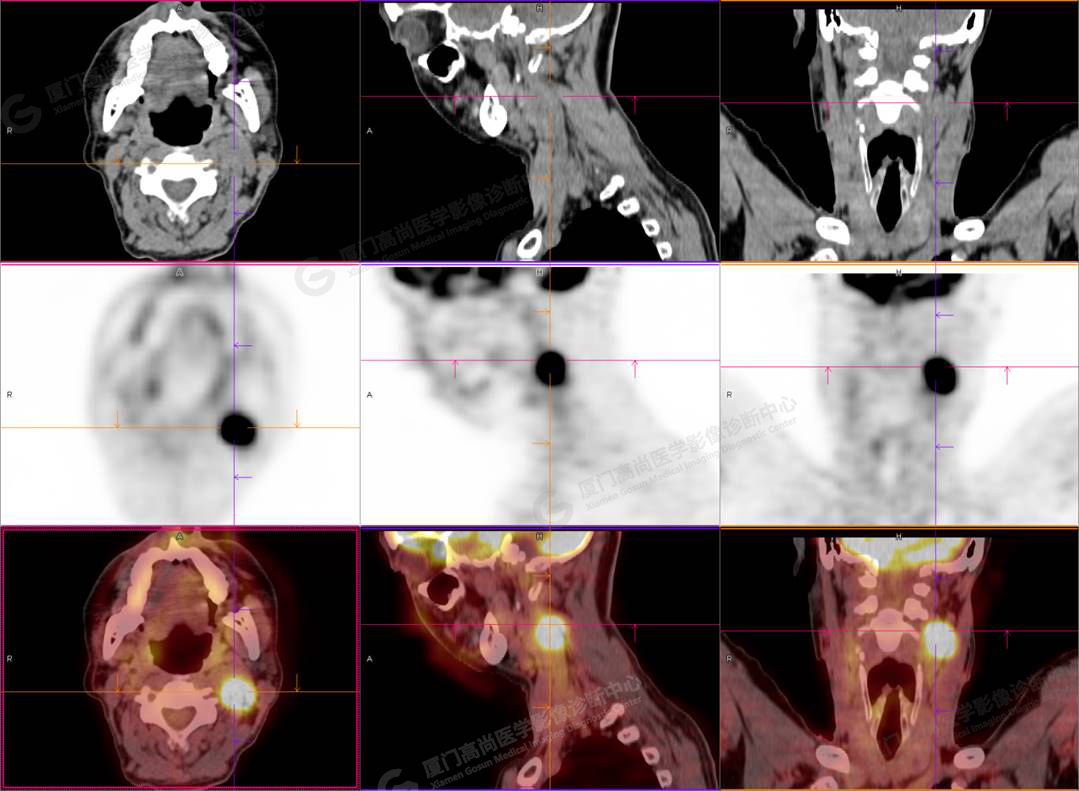

圖1

PET/CT所見:左側(cè)頸部(II區(qū))見腫大淋巴結(jié),大小約2.5cm×2.3cm,其內(nèi)密度不均,邊界尚清,放射性攝取異常增高,早期SUVmax 11.5,延時SUVmax 14.5。

影像診斷: 左側(cè)頸部(II區(qū))腫大淋巴結(jié),代謝異常增高,考慮腫瘤性病變可能性大(淋巴瘤?轉(zhuǎn)移瘤?),建議病理學(xué)檢查明確。